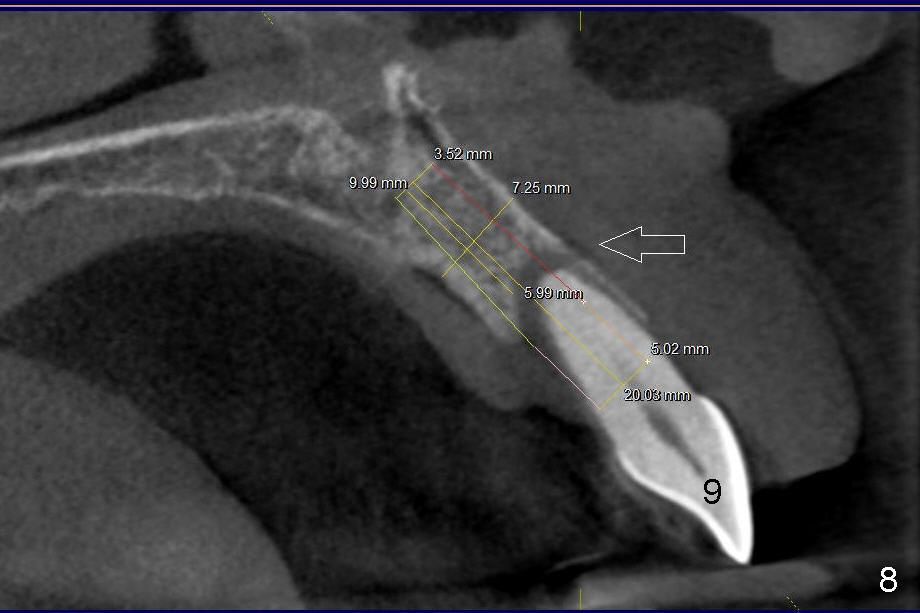

10. Then ext #7, curettage, rinse, antibiotic soak, rinse, pilot drill (Bicon, possible with drill extension)

12. Bicon reamers, save bone, later mix with synthetic bone (Osteogen), reamers until 3.0 mm for #7, 3.5 for #6, tap 4.5x20 for 6, then 5x20, possibly 6x20

14. Place implants as palatally as possible. Use Tatum tapered drills if orientation changes unfavorably